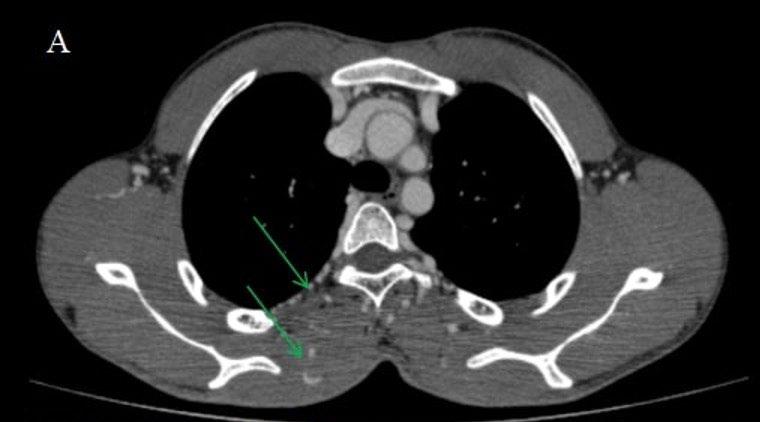

Create a flipbook